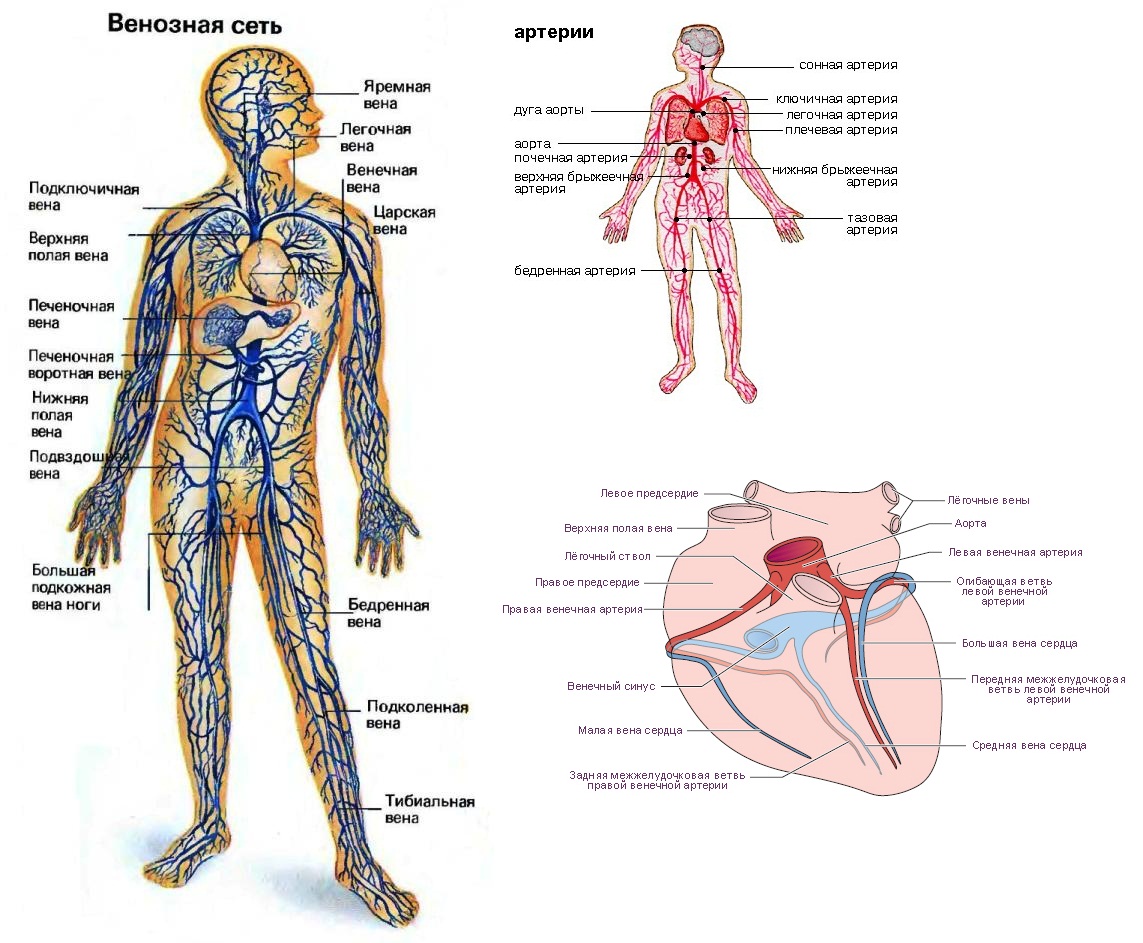

Анатомия человека: кровеносная система и её связь со скелетом

Раздел: Моменты озарения